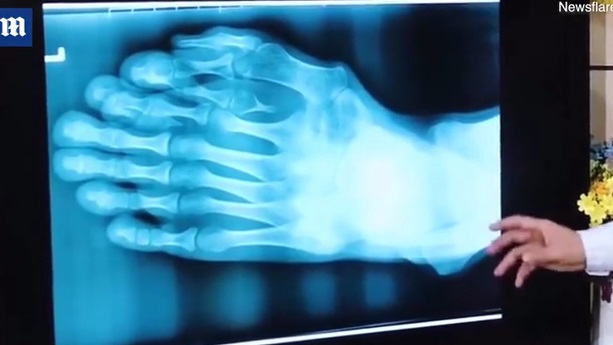

Se trata del chino Ajun, quien nació con nueve dedos en el pie izquierdo. Esta deformidad le causó graves problemas de autoestima en su infancia.

Sin embargo, más allá de un tema estético, una serie de radiografías revelaron que su condición podría empeorar y afectar su extremidad, ya que tenía dedos más pequeños brotando.

“Es muy raro ver una deformidad tan grave que no haya sido tratada en un paciente de 21 años”, señaló el doctor Wu Xiang, quien tras 9 horas de operación, logró quitar los sobrantes y reconstruir un dedo gordo.